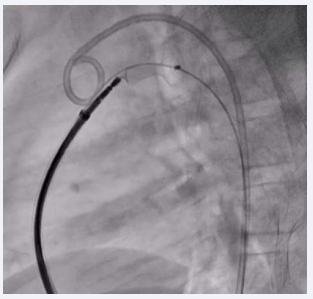

The Terumo wire was then gently removed, and the device was released in place (Figure 4,5).

Figure 5 Final fluoroscopic image showing PDA device in place after release.

Figure 5: Final fluoroscopic image showing PDA device in place after release.